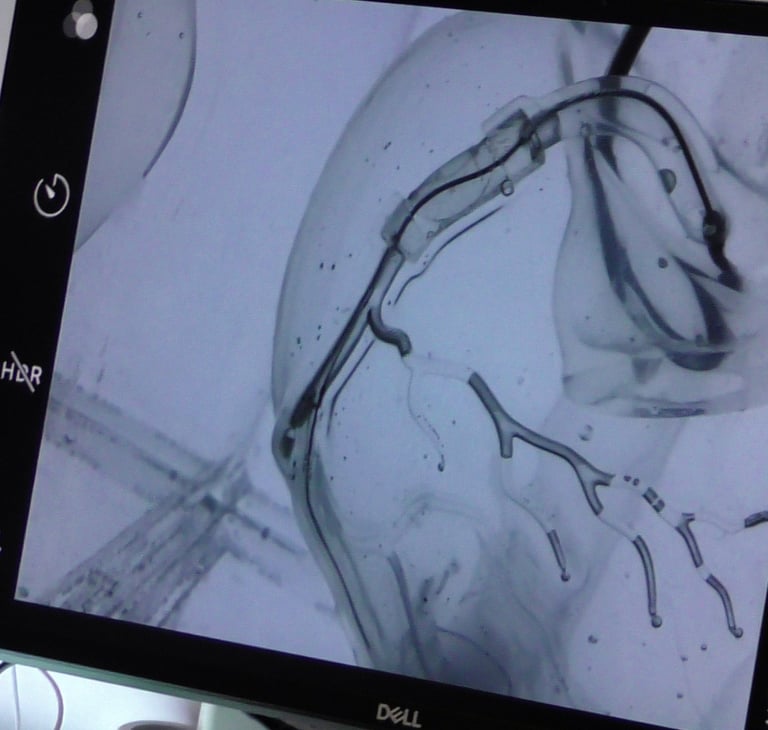

La cardiologie interventionnelle est une profession médicale passionnante. Son objectif principal est de repousser les limites de la cardiologie en utilisant des techniques avancées pour traiter les maladies cardiaques. Grâce à notre passion pour la recherche, nous sommes constamment à l’affut de nouvelles découvertes et de nouvelles technologies pour améliorer les soins aux patients.